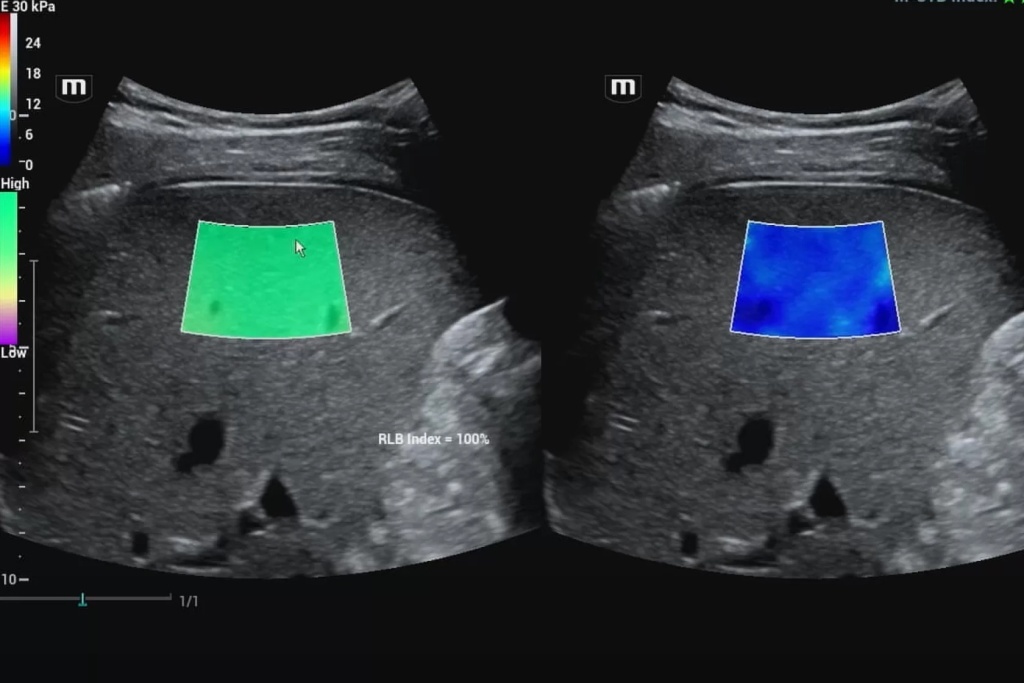

С применением методик эластографии жесткость интересующей нас зоны поверхностно-расположенных и внутренних органов может быть оценена и представлена в виде цветовой эластограммы, наложенной на изображение в В-режиме, и количественно. Это лежит в основе дифференциальной диагностики различных патологических изменений в структуре органа.

В данном случае получение абсолютных значений модуля Юнга (характеризующего жесткость тканей) невозможно, так как его значения зависят от приложенной силы, величина которой не стандартизирована и неизвестна. Поэтому проводится сравнение величины деформации, или стрейна. При воздействии одинаковой силы менее деформируемые ткани являются более жесткими, а более деформируемые – менее жесткими. Ультразвуковой сканер, работающий в специальном режиме, позволяет оценить и сравнить величину деформации тканей в окне опроса и картировать их соответствующим цветом, а также провести полуколичественную оценку – определить отношение деформации в зоне интереса и референсной (условно здоровой) ткани – StrainRatio.

Эластография сдвиговой волной позволяет получить абсолютные значения жесткости исследуемой ткани. В основе данного метода лежит оценка скорости распространения поперечной (боковой) волны, которая может вызываться кратковременным механическим воздействием определенной силы и продолжительности на поверхность тела пациента (это так называемая транзиентная эластография) или сфокусированным усиленным акустическим импульсов в толще исследуемой ткани (именно данные методики в литературе обозначаются как эластография сдвиговой волной). Они в свою очередь подразделяются на методики точечной и двумерной эластографии.